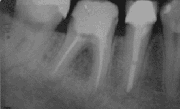

- bei einer resorbierenden apikalen Parodontitis (röntgenologisch sieht man eine Aufhellung an der Wurzelspitze);

Nach Durchführung einer Lokalanästhesie erfolgt die Mobilisierung eines Mukoperiostlappens (Zahnfleischlappen). Anschließend wird mit einer Kugelfräse unter Kühlung mit physiologischer Kochsalzlösung der Knochen über der Wurzelspitzenregion entfernt (Osteotomie) und der pathologische Befund entsprechend seiner Ausdehnung dargestellt. Das granulomatös entzündliche oder zystische periapikale Gewebe wird entfernt und die Wurzelspitze abgetrennt und geglättet. Am Resektionsquerschnitt wird die Wurzelkanalfüllung auf Dichtigkeit überprüft, gegebenenfalls muss die Wurzelkanalfüllung erneuert oder eine retrograde Wurzelfüllung gelegt werden. Dabei werden die Wurzelkanäle von der Gegenseite, d. h. an der Wurzelspitze, im Rahmen einer Wurzelspitzenresektion verschlossen.